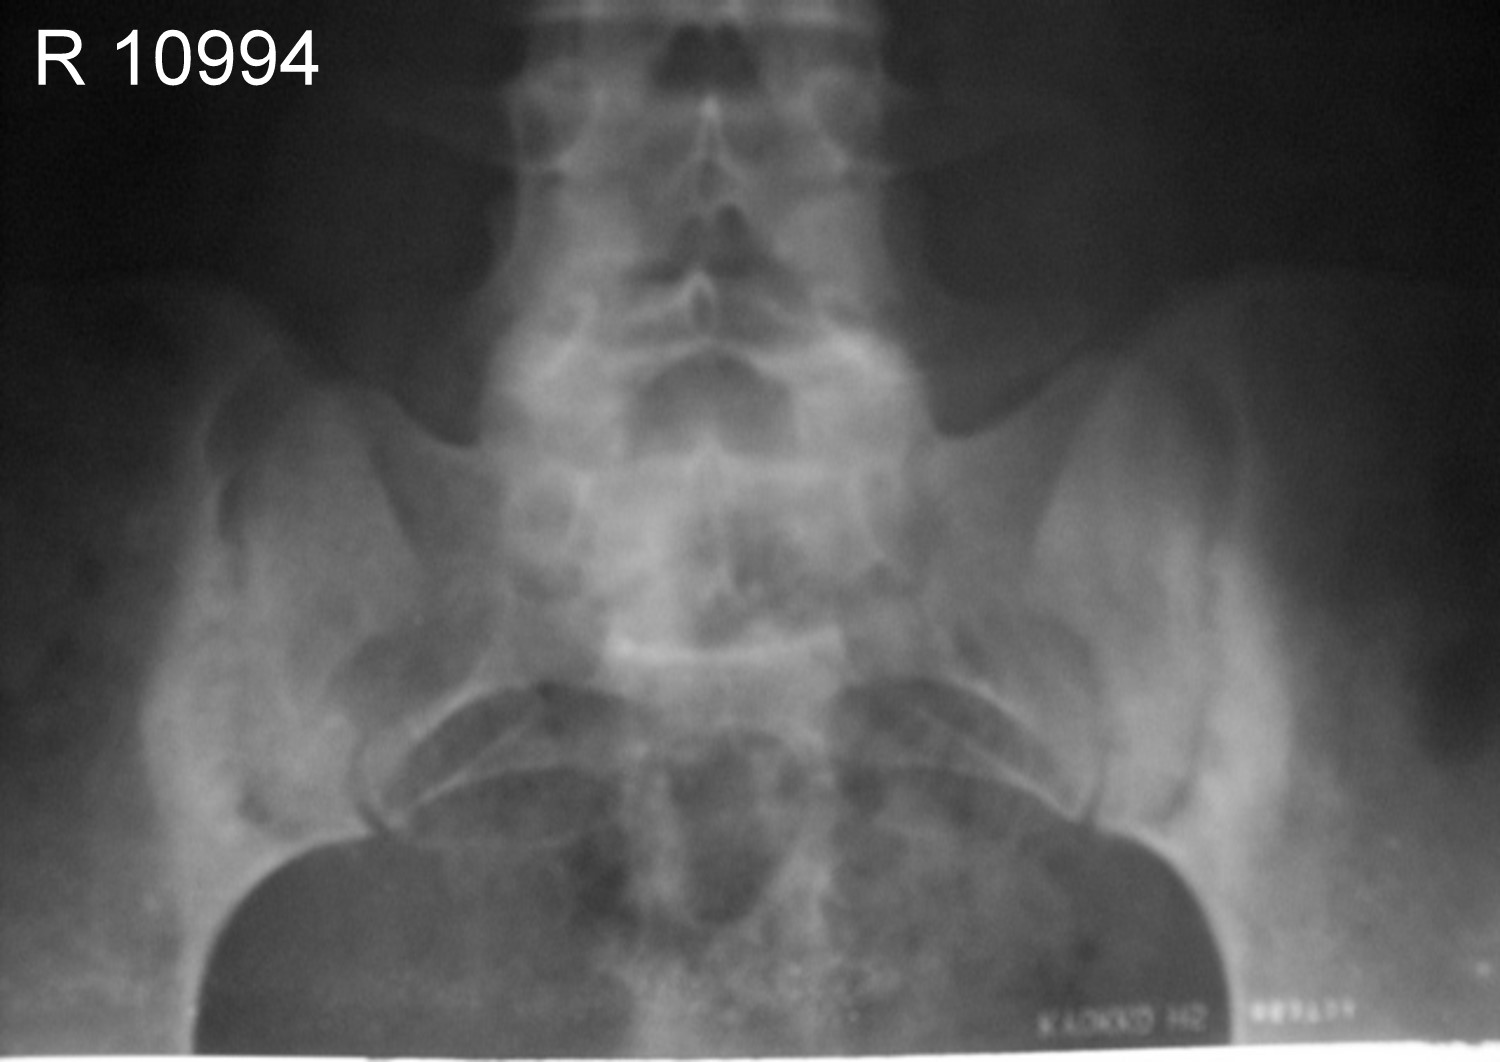

Sacro-Iliac joints of same patient A.P view